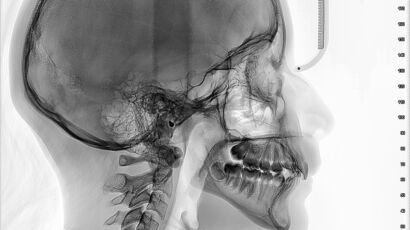

Un examen de tomografía computarizada (TAC) macizofacial es una herramienta diagnóstica esencial en la…

El examen de TAC macizofacial, o tomografía axial computarizada macizofacial, es una técnica de…